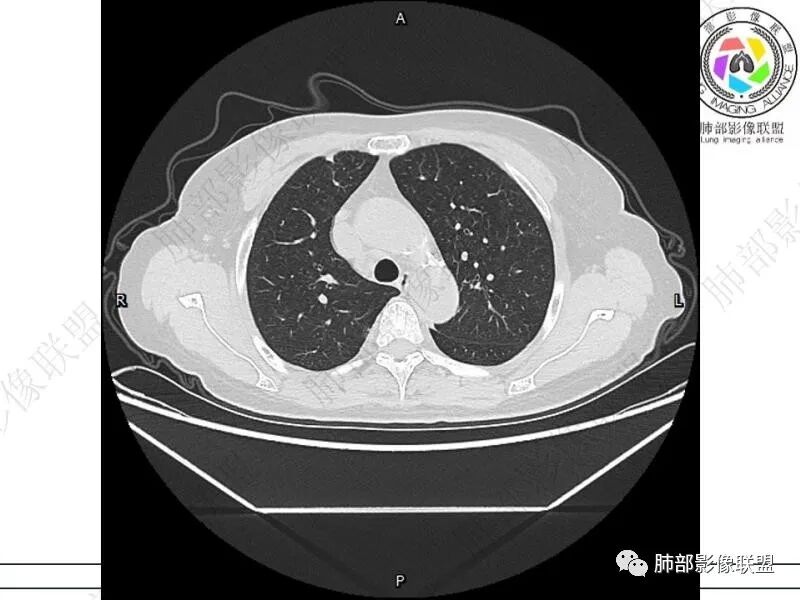

摘星空竹子:两肺胸膜下多发实性结节、磨玻璃影及实变影,短期复查病变有所进展,考虑感染性病变,隐球菌可能,患者有右半结肠癌手术史,转移不能除外。

简单:双肺及胸膜下多发小结节,双下肺胸膜下宽基底团块影,短期内病灶进展考虑炎性病变,隐球?患者ca术后,双肺小结节随诊除外转移

丽:双肺下叶胸膜下多发片状高密度影,边缘模糊不清,内可见支气管穿行,病变长轴平行于胸膜,考虑感染性病变,隐球菌

媛:肠癌术后,免疫力低下。两肺胸膜下结节及实变影,实变影长轴平行于胸膜,密度均匀,边界偏清,周围有晕征,短期复查进展,虽隐球菌荚膜抗原检测阴性,还是考虑隐球菌,鉴别OP

谢加平:结肠癌术后史,两肺胸膜下多发结节及斑块实变病灶,实边边界平直征(亚急性和慢性病变过程),双肺下叶后基底段胸膜下为甚,与胸膜平行特点,见支气管充气征,边缘模糊的GG0,首诊2022年11月18日肺部CT,与治疗11月28日对比,病灶未吸收,双肺下叶胸膜下病灶有侧向融合特点,综合分析符合炎性肉芽肿,隐球菌感染。

老年女性,结肠癌术后。两下肺胸膜下为主片状实变,右下肺短期复查融合且病灶长轴平行于胸膜,实变内可见支气管充气征,边缘磨玻璃晕,另两肺内胸膜下散在数枚小结节状、楔形实性灶。考虑感染性病变,隐球菌可能,鉴别肺转移。

2.影像特征:双肺胸膜下多发实性结节、磨玻璃影及实变影,胸膜下优势分布、晕征、胸膜下脂肪间隙存在,部分病灶边界平直征,有侧向融合趋势。